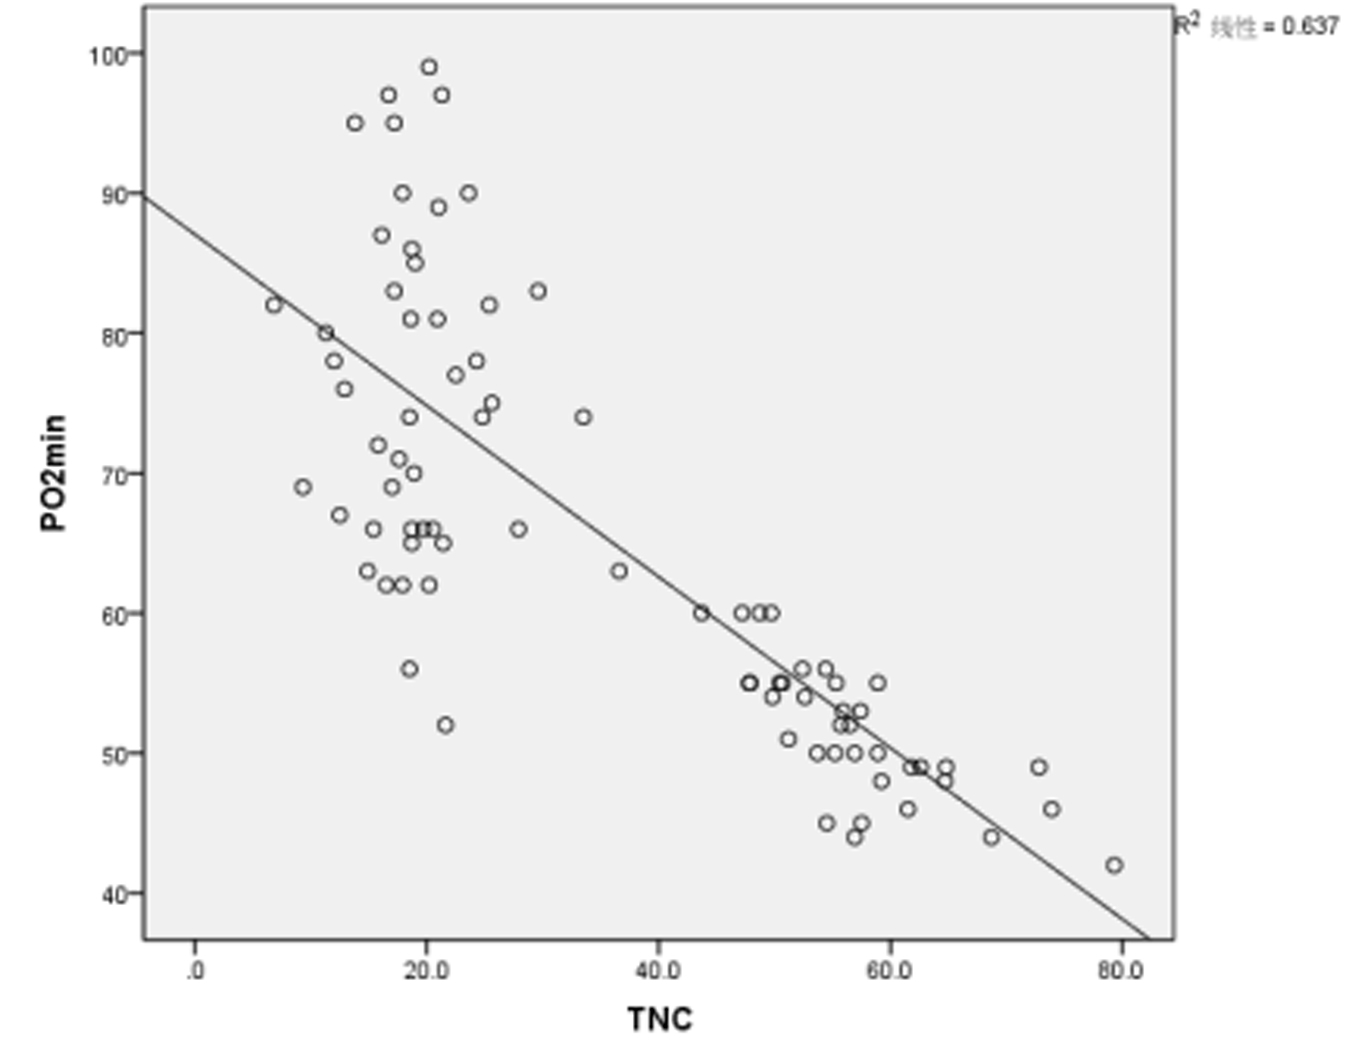

相关性分析显示,PQ中毒患者首诊血清TNC浓度和来诊72 h最差氧分压(PaO2min)呈显著负相关(r=-0.801,P < 0.01),另外与pHmin、PaCO2min、Lacmax、72 h肺CT阳性率亦具有相关性,而与ALTmax、Crmax、BUNmax等无明显相关性。如表 5及图 2所示。

| 图 2 首诊血清TNC浓度与来诊72 h PaO2min相关性 Fig 2 Correlation analysis of serum TNC level on admission and PaO2min at 72 h after diagnosis |

进一步分析首诊血清TNC浓度与患者来诊72 h最差生化指标的关系,发现入院首次血清TNC水平与72 h内PaO2min相关性最大,即血清TNC浓度越高,相应的PaO2越低,肺损伤越重。而动物实验结果表明TNC在急性肺损伤后一周达到表达峰值,而且后续表达与持续肺损伤程度以及损伤后过度修复所导致的纤维化密切相关[8]。虽然本研究未连续监测血清TNC表达变化,但结合动物实验结果,笔者认为TNC作为急性PQ中毒肺损伤标志物具有早期敏感度高,持续表达时间长,特异性较高等特点,值得临床进一步研究和应用。